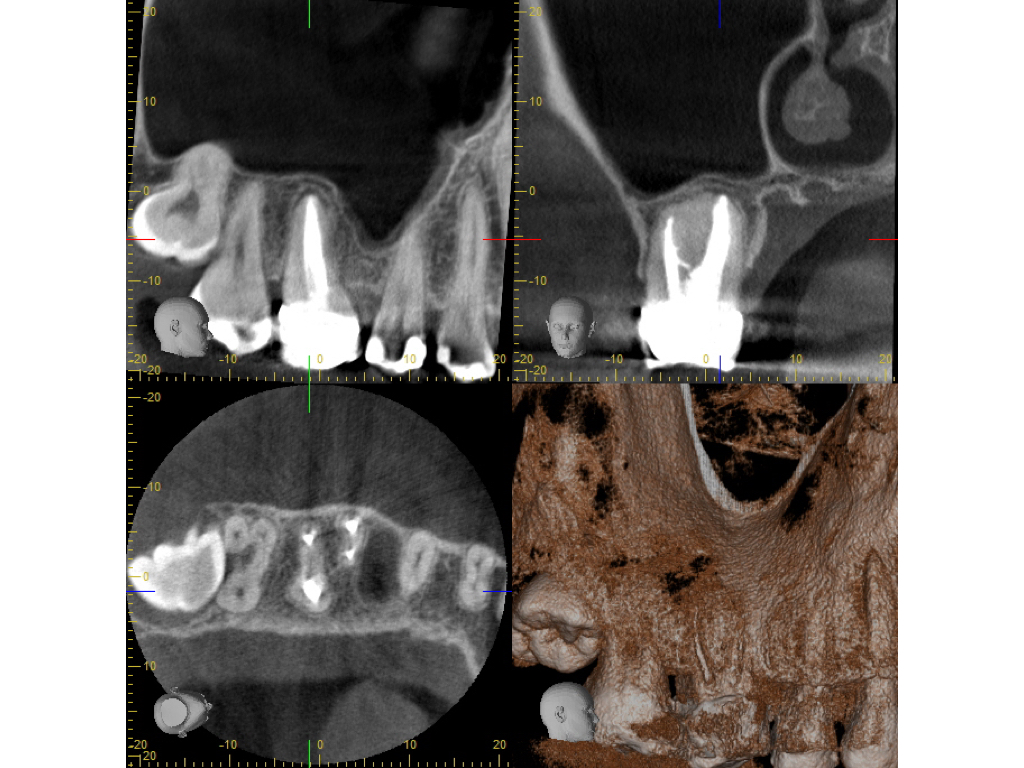

wsi-ti7848-007

Healing?

DVT 2 Jahresrecall